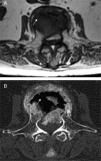

She consulted for low inflammatory back pain lasting 4 weeks, with no history of trauma, fever or constitutional symptoms. The lateral lumbar spine X-ray showed a fracture of L3 due to collapse with intravertebral vacuum phenomenon (IVVF), suggesting vertebral osteonecrosis (ON). Computed tomography (CT) and magnetic resonance imaging (MRI) confirmed this diagnosis (Figs. 1–3). Surgical fixation was performed of the area. The study showed histological signs of bone avascular necrosis: trabecular bone tissue with extensive areas of necrosis, medullary space with proliferation of granulation tissue, few hematopoietic elements, necrosis and cellular debris.

IVVF, although not pathognomonic, is the most characteristic radiographic sign of this entity and often suggests the diagnsis.3,4 This sign reflects the presence of gas within the bone (mainly nitrogen) and in adjacent tissues. IVVF can be seen in radiographs, a linear or crescent-shaped radiolucent image usually located adjacent to the superior endplate, which appears or is enhanced by the extension, and decrease or even disappears with flexion of the spine. Sometimes it can be detected by CT or MRI because of its greater sensitivity.